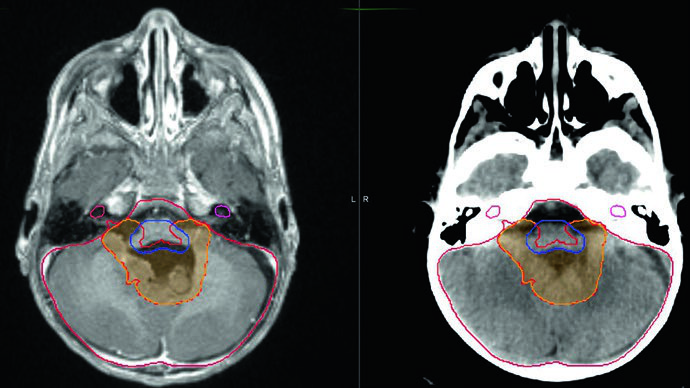

Volúmenes para boost de fosa posterior completa

| Volumen | Definición |

|---|---|

| GTV | Lecho tumoral con enfermedad residual, paredes de la cavidad y áreas señaladas por el neurocirujano. |

| CTVFP | Toda la fosa posterior incluyendo el tronco cerebral completo. Límites: base del cráneo anteriormente, tentorio superiormente, foramen magno inferiormente. El hueso del cráneo restringe posterior y lateralmente. |

| PTVFP | CTVFP + 3 a 5 mm según frecuencia de imagen y experiencia institucional. |

Fuente: Target Volume Delineation and Field Setup, 2nd Edition (Table 34.3)